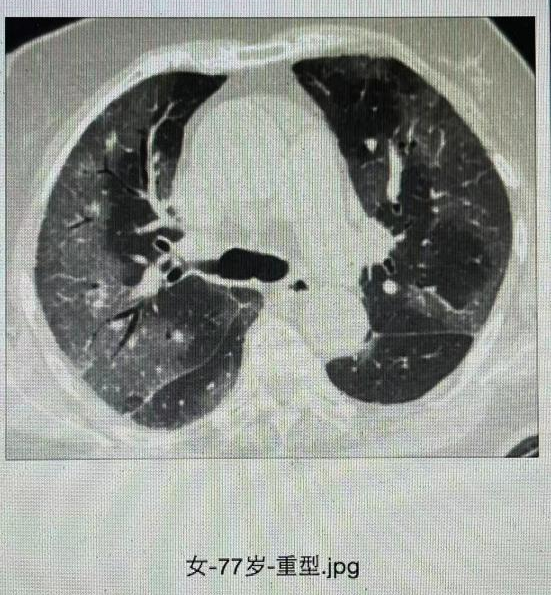

(三)重型

符合下列任何一条且不能以新型冠状病毒感染以外的其他原因解释:

1. 出现气促,RR≥30次/分;

2. 静息状态下,吸空气时指氧饱和度≤93%;

3. 动脉血氧分压(PaO2)/吸氧浓度(FiO2)≤300mmHg(1mmHg=0.133kPa),高海拔(海拔超过 1000 米)地区应根据以下公式对 PaO2/FiO2进行校正:PaO2/FiO2×[760/大气压(mmHg)];

4. 临床症状进行性加重,肺部影像学显示24~48小时内病灶明显进展>50%。

图 重型新冠感染的CT表现